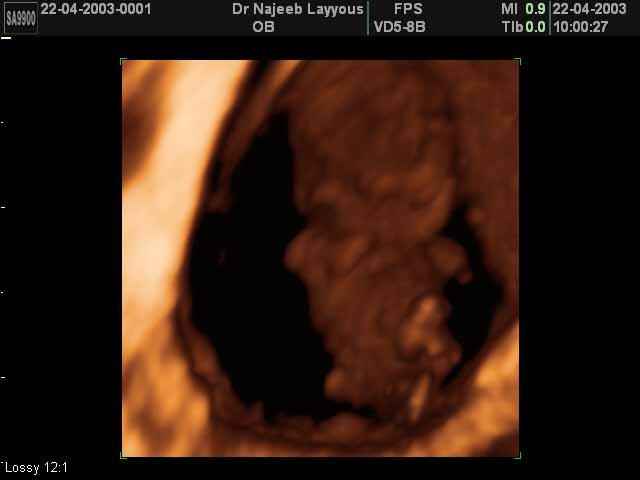

3D First Trimester Ultrasound Scan Photos ( Early Pregnancy Ultrasound Photos ) | Dr N Layyous